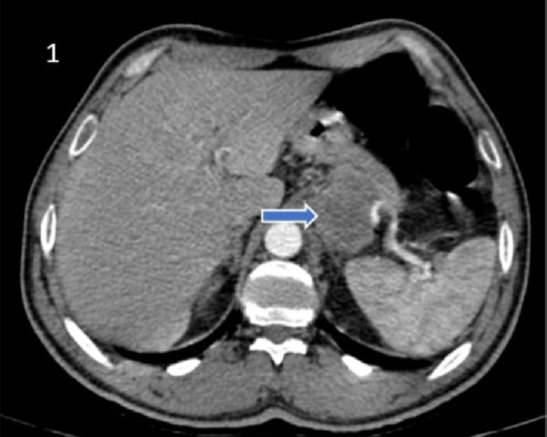

Pancreatic carcinosarcoma is one of the rare malignant tumors of the pancreas. Although they are aggressive, they can be detected with local or distant organ metastases when detected. In this article, the surgical procedure applied to pancreatic trophoblastic carcinosarcoma, which showed local invasion in a patient who applied to the emergency department of our hospital with the complaint of bloody vomiting and was operated with a preliminary diagnosis of gastric hemorrhage, the pathology result and the aggressive progression of the disease in a short time were presented. A literature review was conducted for pancreatic trophoblastic carcinosarcoma, which is a rare case, and the findings were presented.